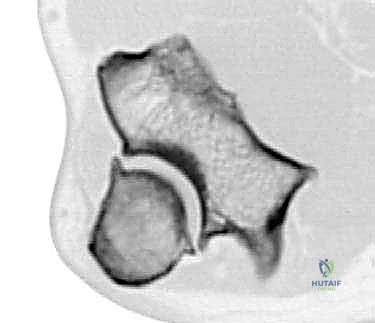

However, radiographs often don't fully delineate all osteophytes. For surgical planning, especially when considering open débridement or arthroplasty, a Computed Tomography (CT) scan is indispensable. It provides detailed structural anatomy, accurately localizing osteophytes and loose bodies, and helps us visualize the extent of articular surface involvement. Three-dimensional reconstructions from CT data are particularly valuable for planning osteophyte removal.

FIG 2 C: Computed tomography of the elbow demonstrating marginal osteophytes on the ulna and olecranon fossa.